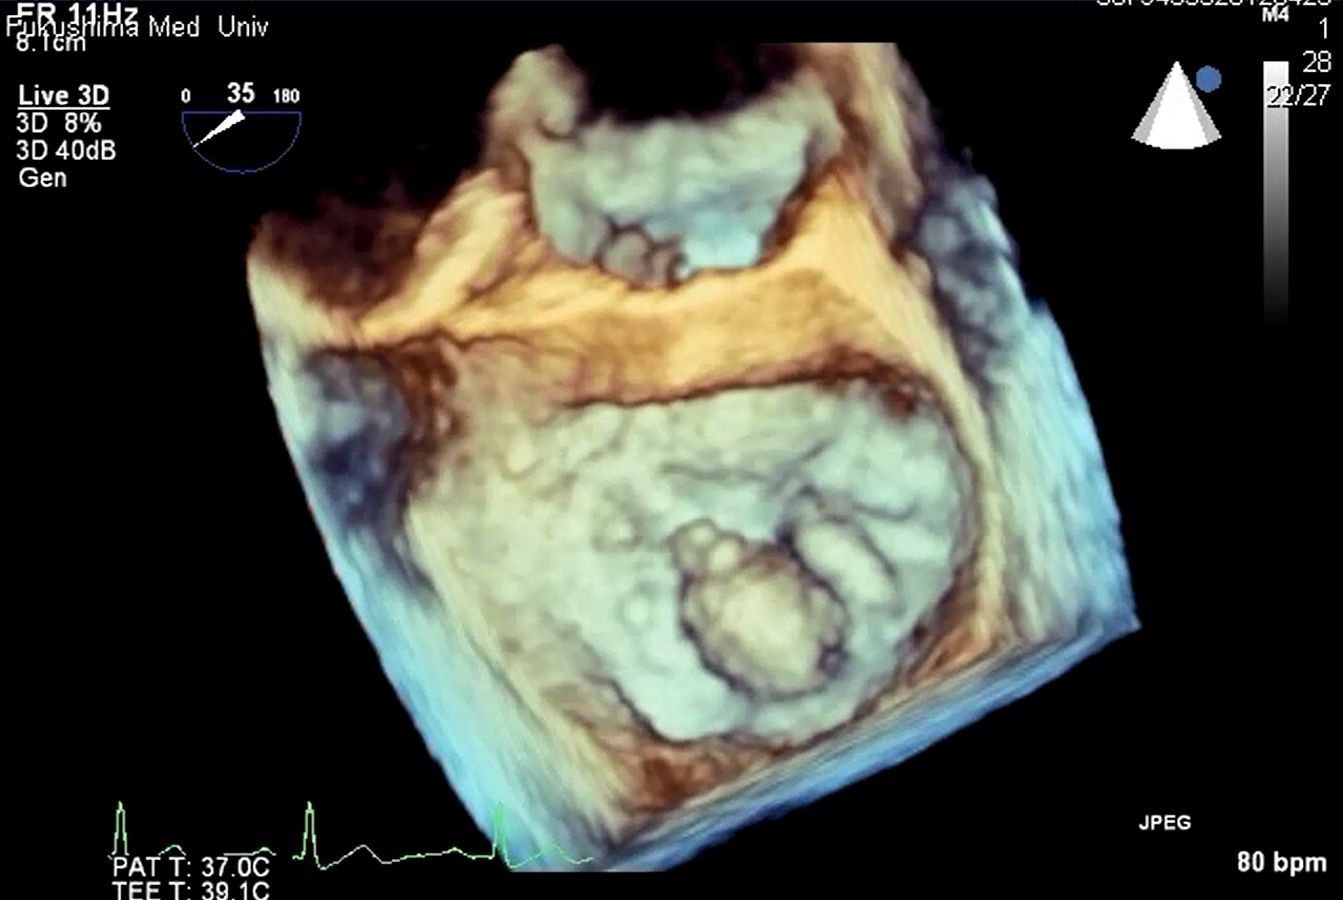

3D画像

僧帽弁逸脱症候群(僧帽弁後尖逸脱)

左心耳血栓

心房中隔欠損症